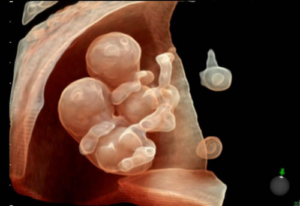

Σας καλωσορίζουμε στο Ιατρείο Εμβρυικής Ιατρικής και Προγεννητικού Ελέγχου στη Λ. Αλεξάνδρας (Mamalis Fetal Medicine).

Προσφέρουμε εξειδικευμένη και εξατομικευμένη φροντίδα στην έγκυο και το μωρό της, εφάμιλλη γνωστών κέντρων του εξωτερικού, όπως το King’s College Hospital στο Λονδίνο και το Universitätsklinikum Giessen & Marburg στη Γερμανία, στα οποία εξειδικεύτηκε ο Dr. med. univ. Μάριος Μάμαλης κατά τη δεκαετή του παραμονή στο εξωτερικό.